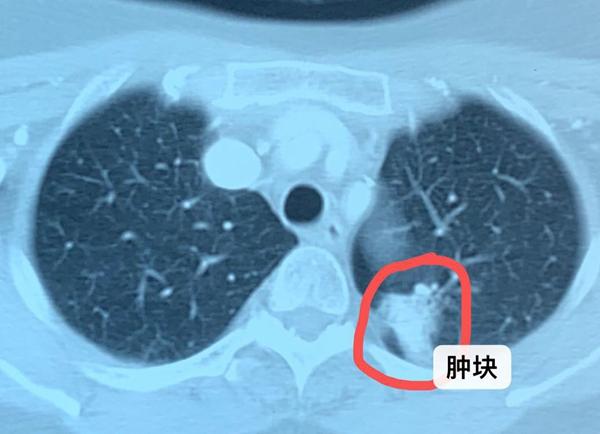

我们知道肺癌是一个大的总体的名称,其实肺癌的病理学亚型有十几种,比如我们最常见的肺小细胞癌、肺腺癌、肺鳞癌、肺大细胞癌等等。每种病理类型的恶性程度和生长速度并不一样,临床上的确可以发现,在短短几个月内肿瘤从生长一直到发生了全身转移。因此,可能体检的时候还没有出现肿瘤的迹象,但是过一段时间以后就出现了肿瘤的爆发性的生长和转移。

综合判断第一种情况的可能性更大一些,因为在短期内就出现肿瘤生长,并发生全身转移的机会并不大。而采用低度敏感的胸部透视或者胸片检查,常常不能发现小的病灶,因此耽误了诊断。

所以,到目前来说,被公认的早期诊断或者筛查肺癌的手段就是低剂量的螺旋ct。胸部螺旋ct检查可以发现一两毫米以上的病灶,它的敏感性非常高。 因此一般不会造成漏诊,而导致延期诊断和延误治疗。

目前诊断癌症最标准的手段,还是影像学的检查和病理学的确诊。影像学的检查往往通过胸部CT,腹部B超,磁共振等等手段发现生长在体内的肿块。然后对这些肿块进行穿刺等各种方式的活检,进行病理检查,最后确诊。